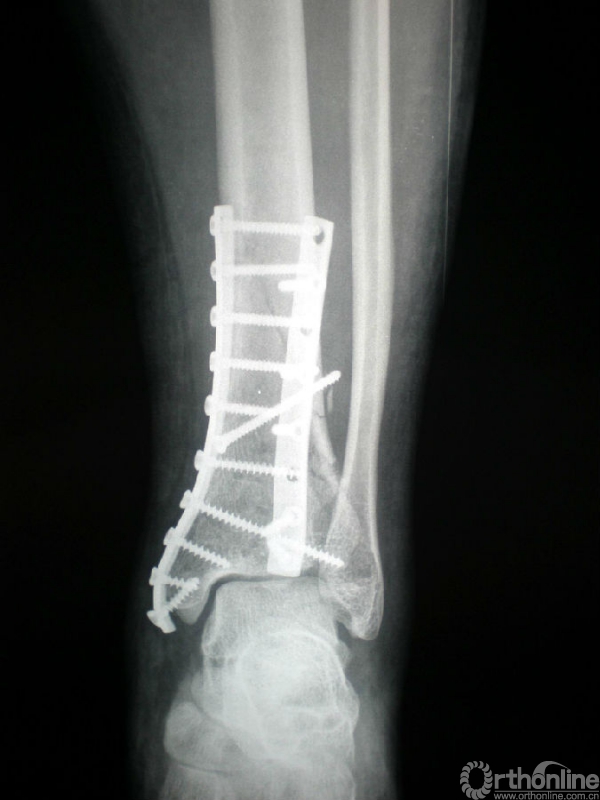

图4 男,41岁,左侧双柱pilon骨折。

4a.术前正位、侧位X线示胫骨远端粉碎性骨折,属于外侧柱的腓骨完整;

4c.手术入路及1/3半管型钢板分柱固定情况;

4d.术后X线正侧位片示双柱pilon骨折对位、对线良好。